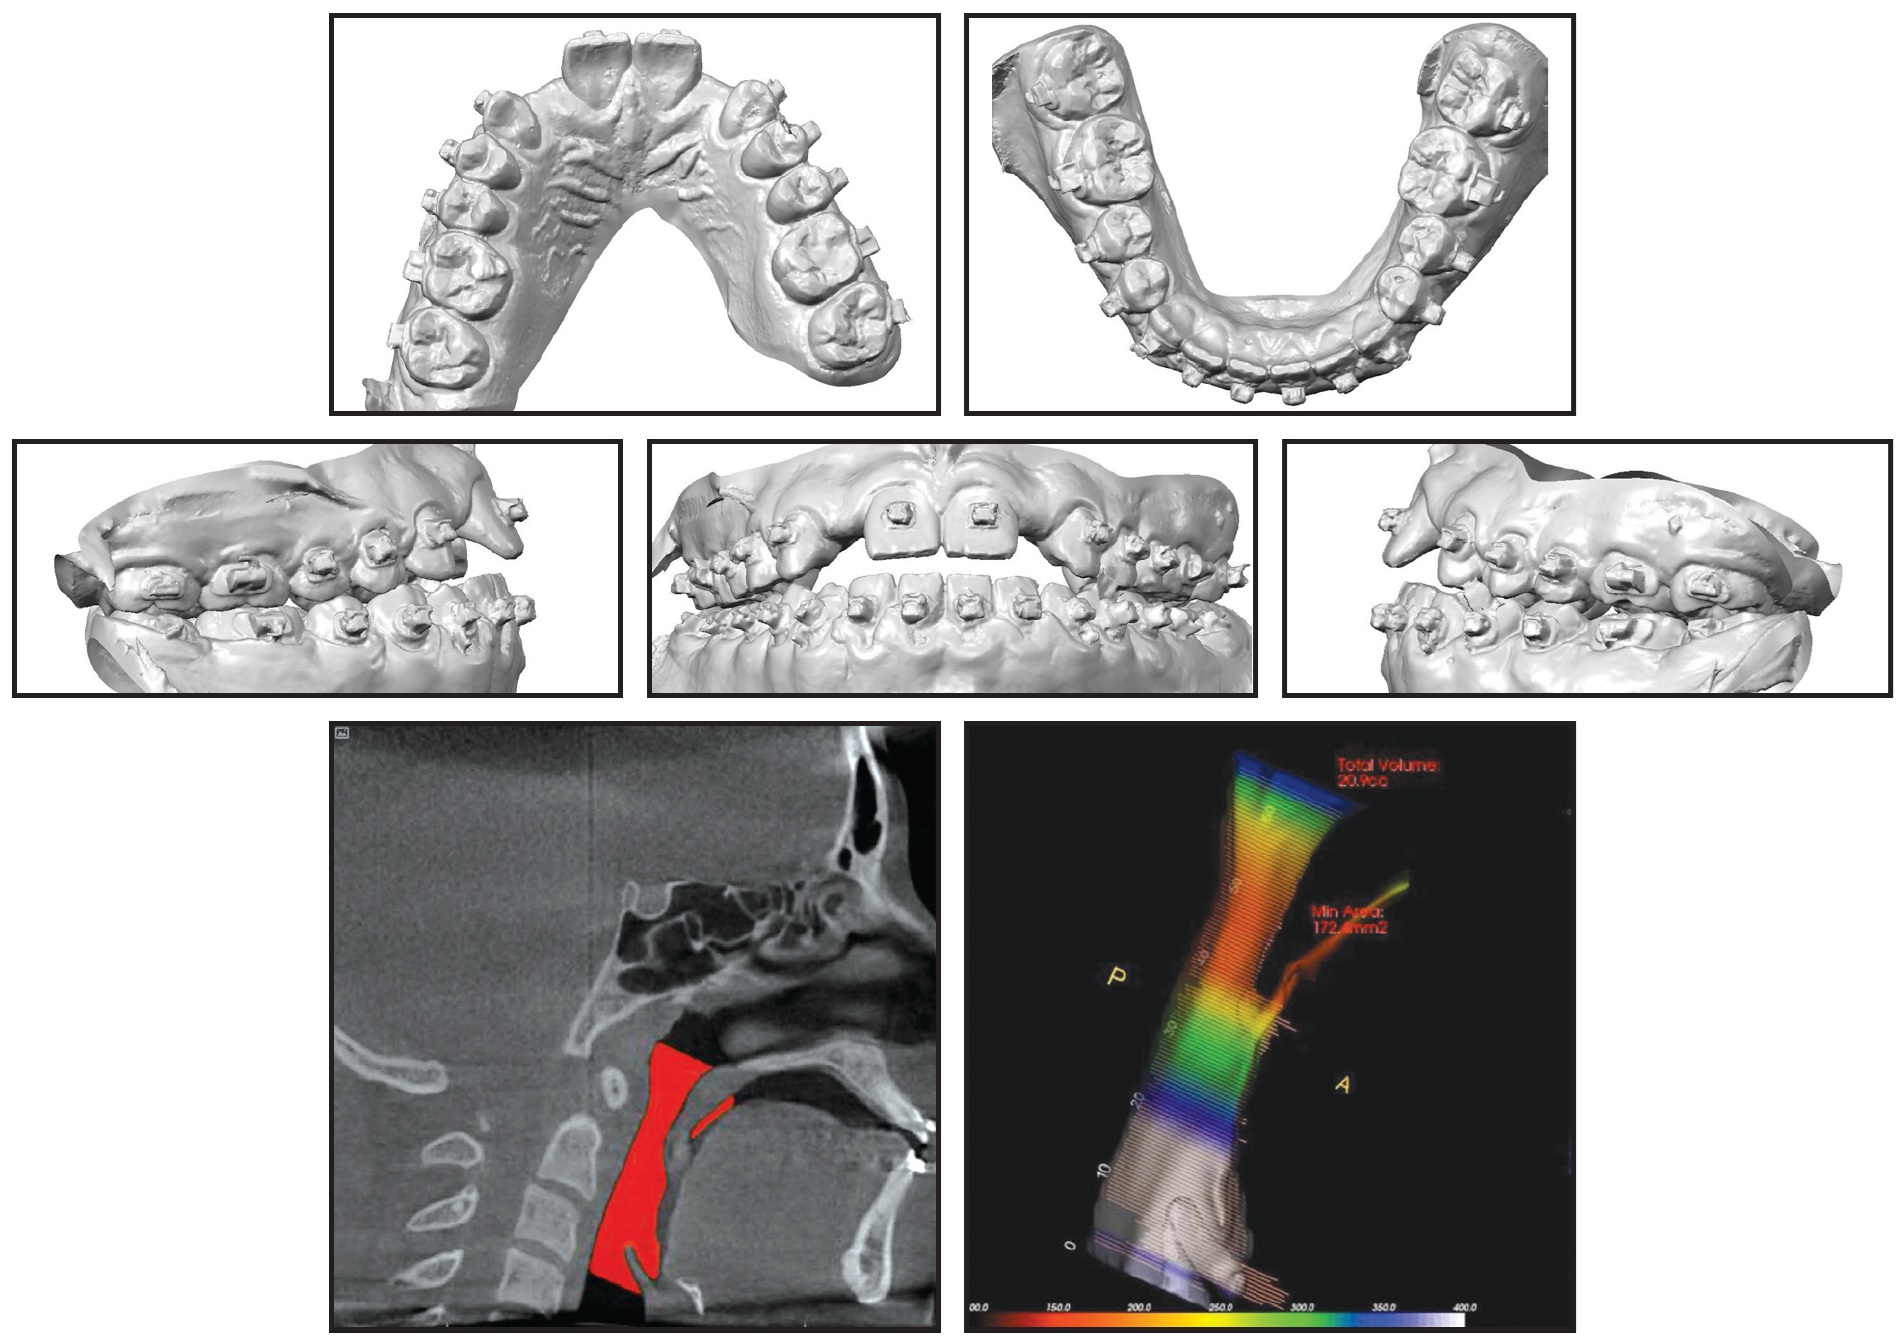

The patient was then scanned for SureSmile custom archwires (Fig. 4).

Fig. 4 SureSmile** simulation.

The patient was referred to the oral surgeon for the maxillary anterior corticotomy and extraction of the third molars (Fig. 5). One week later, .017" × .025" nickel titanium SureSmile archwires were placed for use with vertical elastics. These were followed by .019" × .025" nickel titanium SureSmile and .017" × .025" beta titanium SureSmile archwires (Fig. 6).

Fig. 5 Maxillary anterior corticotomy and bone graft (photos courtesy of Dr. Sherrill Fay).

Fig. 6 Two months after corticotomy.

New SureSmile archwires were ordered to address the need for more mandibular arch expansion and posterior uprighting. The same wire sequence was performed again, and the patient was referred to the prosthodontist for final approval of the tooth positions. After debonding, SureSmile clear aligners were delivered, with esthetic pontics in place of the upper lateral incisors, and a mandibular 3-3 fixed retainer was bonded (Fig. 7).